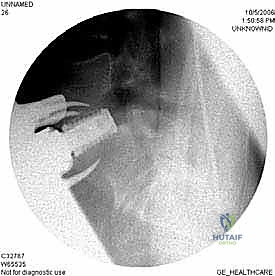

بعد التأكد من وضعية الغرسات باستخدام الأشعة السينية داخل غرفة العمليات، يتم إعادة الأوعية الدموية والأعضاء الداخلية إلى وضعها الطبيعي، وتُغلق طبقات البطن بخيوط تجميلية.